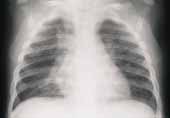

La combinación de edema de la pared bronquial, estrechez de la luz de la vía aérea y tapones mucosos, ocasiona oclusión de la vía aérea pequeña que se manifiesta como aumento del volumen pulmonar y atelectasias segmentarias o subsemegtarias (Figura 2).

FIGURA 2. Proyección Ap de tórax de paciente lactante con evidencia de atelectasias subsegmentarias de

localización central y discreto aumento del volumen pulmonar.

El aumento del volumen pulmonar en ocasiones es más evidente en la radiografía lateral en los niños pequeños.